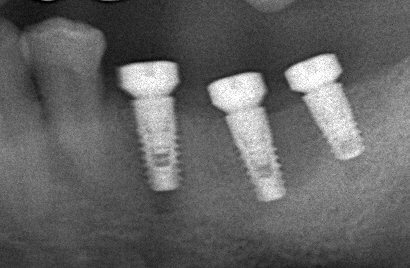

インプラント

自分の歯のように噛むことができる人工の歯

歯を失ってしまい噛めない、また、入れ歯が合わない、わずらわしいなどと思っていらっしゃる方にインプラント(人工歯根を植える)治療を行っております。

歯が抜けた部分の骨に人工歯根を埋め込み、人工の歯を装着する治療法です。

チタン製の小さなネジのような形状のインプラントを局所麻酔下にて顎の骨の中に埋め込みます。